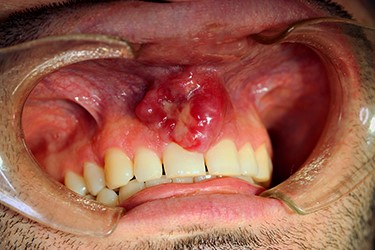

On examination, a lobulated, firm mass was seen extruding from the anterior maxillary vestibule (Fig. 1). All maxillary teeth were painless to percussion, and normal tooth mobility was present. No cervical lymphadenopathy was detected, nor any changes with cranial nerve examination. A maxillofacial computerized tomographic (CT) scan revealed an osteolytic lesion on the maxillary alveolar process (Fig. 2).

Maxillofacial CT scan, axial (A) and sagittal (B) images. Osteolytic lesion on the vestibular edge of the maxillary alveolar process, with 12 mm of craniocaudal dimension and 4 mm of axial dimension.